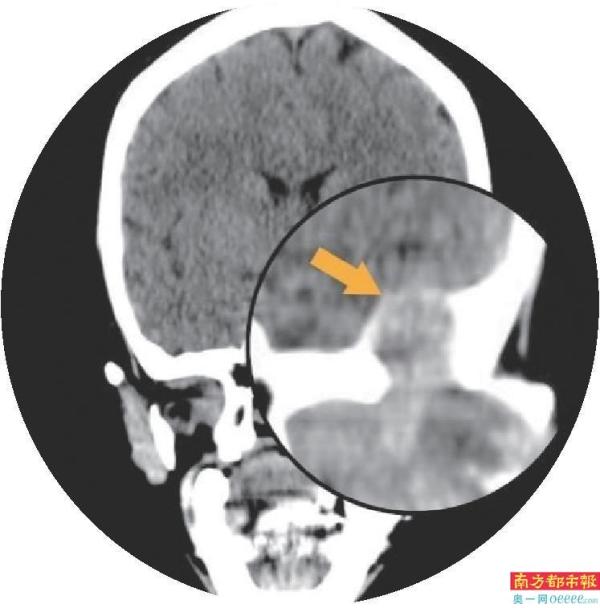

最可怕的是,脸上凸起的肿物只有3cm左右,但是,肿瘤一直往深处发展已经侵蚀到颅底,大概有6×4cm的大小!

“花姐的这个肿瘤是发生在腮腺深叶并向颅内发展的罕见巨大肿瘤,其实腮腺肿瘤并不罕见,但是瘤体巨大,增长较快且侵蚀入颅内的实属罕见。并且这种肿瘤难以发现,早期没有明显的症状与不适,部分患者会出现面部不对称、面瘫(口角歪斜、闭眼不全等)等症状,容易复发甚至恶变,需要尽快手术去除。”张国权主任表示。

而如今,花姐的这个肿瘤位置深,体积大,包绕下颌骨髁状突,穿过下颌升支的内外侧,死死卡在面部深面的颞下窝和翼腭窝,部分瘤体还侵犯到颅内,周围都是重要的血管神经,就像一颗巨大的“地雷”埋伏在那,不仅暴露困难,切除更加困难。

手术难度比普通的腮腺肿瘤手术难度要高得多,并且肿瘤发展迅速,有恶变可能,时间相当紧迫。